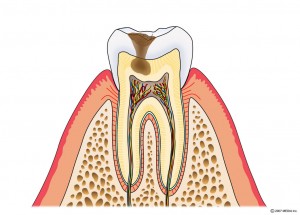

CO:初期むし歯

C1:エナメル質に達するむし歯

C2:象牙質に達するむし歯

C3:歯髄に達するむし歯

エナメル質に達するむし歯

光重合レジン充填・他

象牙質に達するむし歯

光重合レジン充填・部分的な詰め物(型どりを要す物)

歯髄に達するむし歯

歯の神経を取ります→土台を立てます→被せものをつくります。